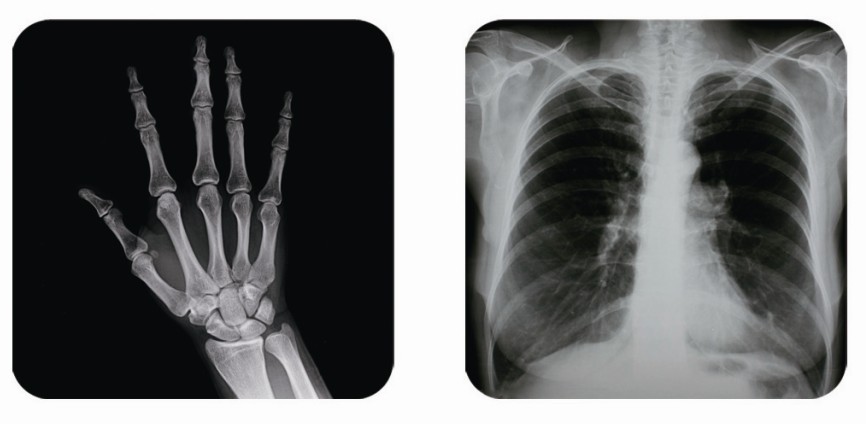

傳統(tǒng)胃腸造影檢查,病變顯示率低,輻射劑量大。普朗醫(yī)療器械公司生產(chǎn)的幾款多功能腸胃造影x光機(jī),更能滿足不同等級不同規(guī)模的大小醫(yī)院選擇,從臨床及科研都很好。尤其最新的PLD8800多功能腸胃造影x光機(jī)用途更為廣泛。多功能腸胃造影x光機(jī)是目前各大醫(yī)院最普及的且用途最廣的一種X光機(jī)。普朗醫(yī)療的胃腸機(jī)功能多,簡便易用,能保證圖像質(zhì)量,該機(jī)采用高制式電視系統(tǒng),優(yōu)秀的數(shù)字化系統(tǒng)能使多功能腸胃造影x光機(jī)的性能得到提高,應(yīng)用范圍獲得極大的拓寬。

1、一般應(yīng)用:數(shù)字透視,動態(tài)及多方位觀察器官病變,圖像更清晰,并可保留末幀圖像;既可使用暗盒完成常規(guī)X線拍片,這是其最大的優(yōu)勢,拍片質(zhì)量大大提高。

2、特殊檢查的應(yīng)用:如“T”管造影、消化道鋇餐、靜脈腎盂造影、子宮輸卵管碘油造影等,在實(shí)時監(jiān)視的同時隨時采集,抓住關(guān)鍵圖像,并可連續(xù)采集,電影回放整個過程。

3、介入方面的應(yīng)用:能很好開展全身各部位的血管造影、藥物灌注、栓塞治療及經(jīng)皮穿刺活檢引流,主要應(yīng)用于血管造影診斷及腫瘤的治療,不明原因腫塊的性質(zhì)確定。